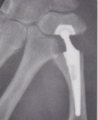

Mise en place d'une prothèse trapézo-métacarpienne : exemple de la prothèse MAÏA® ou de la prothèseTOUCH®